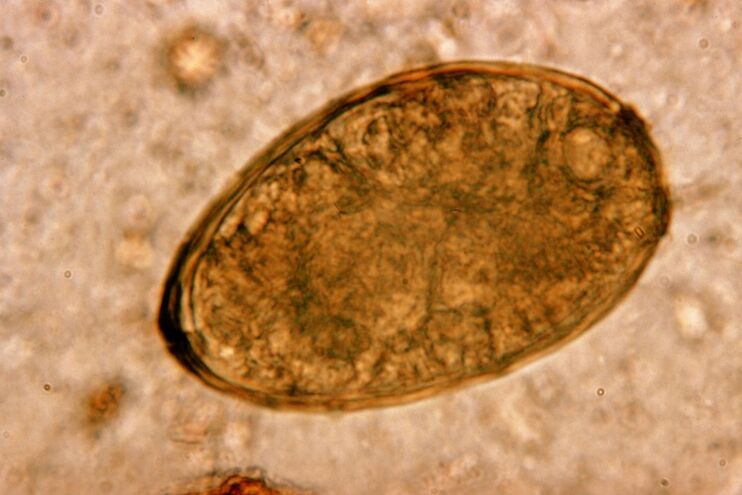

The most dangerous for the respiratory system are flatworms, in particular worms and toxocarriae.When attached to the lungs, they cause paragonimiasis and toxocariasis - serious diseases accompanied by the destruction of lung tissue and a progressive inflammatory process.

The chip lives in the lungs in pairs, forming cysts in the bronchi.Infection occurs by eating crabs and crayfish infected with the parasite.After entering the gastrointestinal tract, pulmonary goiter penetrates the peritoneum and enters the lungs through the diaphragm, which causes a persistent cough in the patient.

A small helminth lungworm belonging to the class of trematodes is "specialized" in parasitizing specifically in the lungs.It causes much more serious problems in the respiratory system than, for example, roundworms.

At the site of its localization, infiltrates appear and hemorrhages develop, resulting in cavities filled with worms, dead parasites, and decaying metabolites of lung tissue.The damage to the lung is further aggravated by the fact that it is a long-liver and can live in the host's body for up to 20 years.